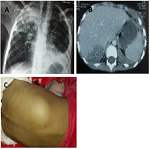

Results: The cohort comprised children from 34 different families, including 12 siblings. The age of onset ranged from 4 days to 13 years, with the diagnosis being established between the ages of 25 days and 13 years. The predominant clinical manifestations were skin infections, lymphadenopathy, pneumonia, BCGitis, liver abscess, pulmonary aspergillosis, and inflammatory colitis. The most frequently isolated germs were Aspergillus, Serratia, and Staphylococcus. Among the total of 42 patients, 17 fatalities occurred, with aspergillosis being identified as the primary cause of their deaths.

Conclusions: In this study, the clinical characteristics and isolated microorganisms correspond to the pathogens known to be important in CGD. Lung infections represent the most prevalent complication and significantly contribute to high mortality rates, particularly in the case of Aspergillus pneumonia, which is known for its tendency to disseminate. Additionally, BCGitis has been frequently observed in countries where the BCG (Bacille Calmette-Guérin) vaccination is routinely administered. Enterocolitis emerges as the most common inflammatory complication in clinical settings. Unfortunately, CGD remains largely unknown in Morocco, highlighting the urgent need to raise awareness among doctors. This increased awareness could facilitate early diagnosis and improve patient prognosis.